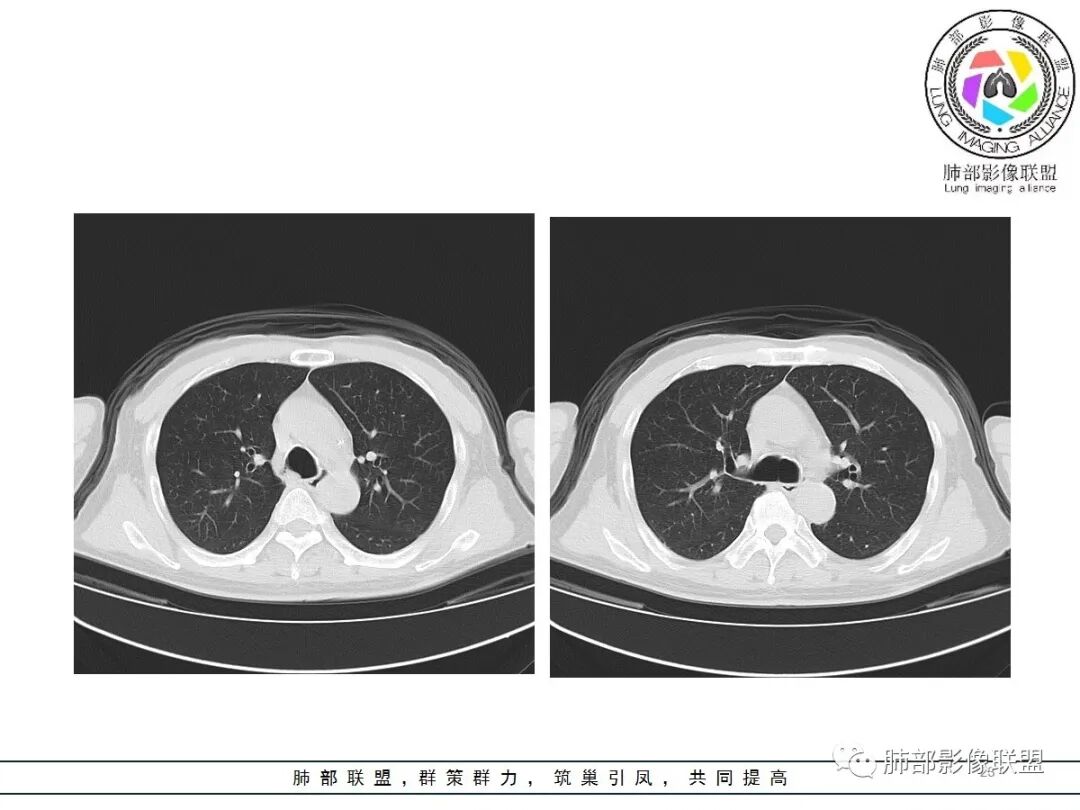

影像:双肺对称性中内带为主分布磨玻璃影,实变不明显。无胸水及小叶间隔增厚。

病史中D2聚体明显升高,影像:双肺对称性中内带为主分布磨玻璃影,有坠积感,实变不明显,胸膜下回避。无胸水及小叶间隔增厚;肺水肿?感染?建议CTPA检查除外肺栓。

CT示双肺中内带多发斑片状磨玻璃影,沿支气管血管束分布,边界模糊,部分支气管壁增厚。定位气道来源的病变,考虑非典型病原体感染,鹦鹉热可能。

1.间质性肺水肿:小叶间隔增厚,尚光滑,支气管血管束增粗,肺血管影模糊,胸膜或叶间裂增厚,肺内有磨玻璃密度影,常有重力分布趋势。

(1)中央型分布:以肺门为中心,两肺中内带对称分布的大片状实变,称为“蝶翼征”。常见于心源性及肾源性肺水肿患者。也可表现为磨玻璃密度病灶,弥漫性分布或以小叶中心性分布。